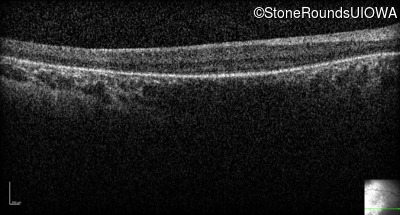

Optical Coherence Tomography - Right - No Light Perception

Exemplar / OCT Stack